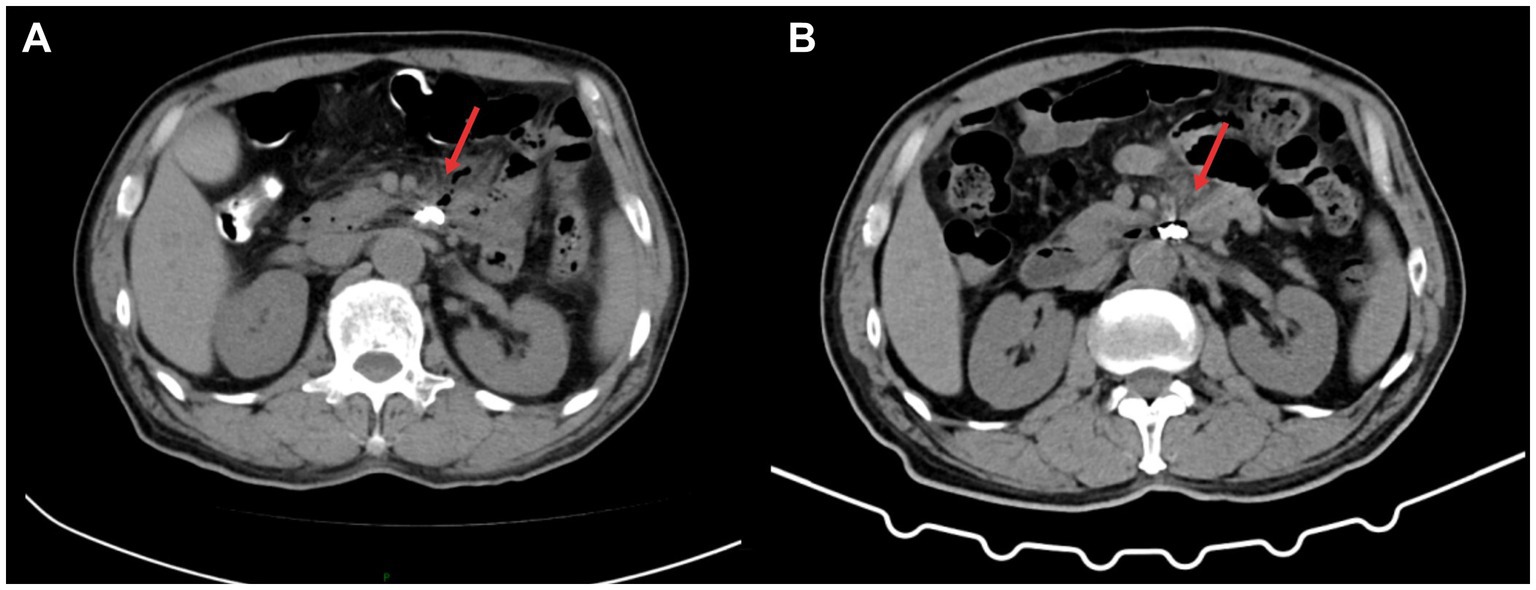

Figure 3

Postoperative follow-up. (A) Abdominal CT: Post-treatment appearance of a duodenal diverticulum in the third portion with perforation. Metallic clips are visible in the surgical area, and there is a reduction and absorption of the gas shadow anterior to the cystic structure compared to before (indicated by the arrow). (B) Abdominal CT: Post-treatment appearance of a third portion duodenal diverticulum with perforation. Metallic clips are visible in the surgical area, and there is no significant display of the gas shadow anterior to the cystic structure (indicated by the arrow).